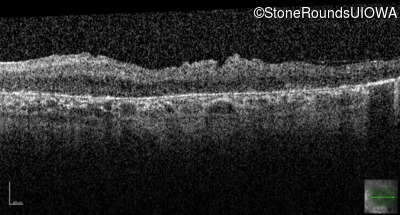

Optical Coherence Tomography - Left - Light Perception

Exemplar / OCT Stack

OCT Stack